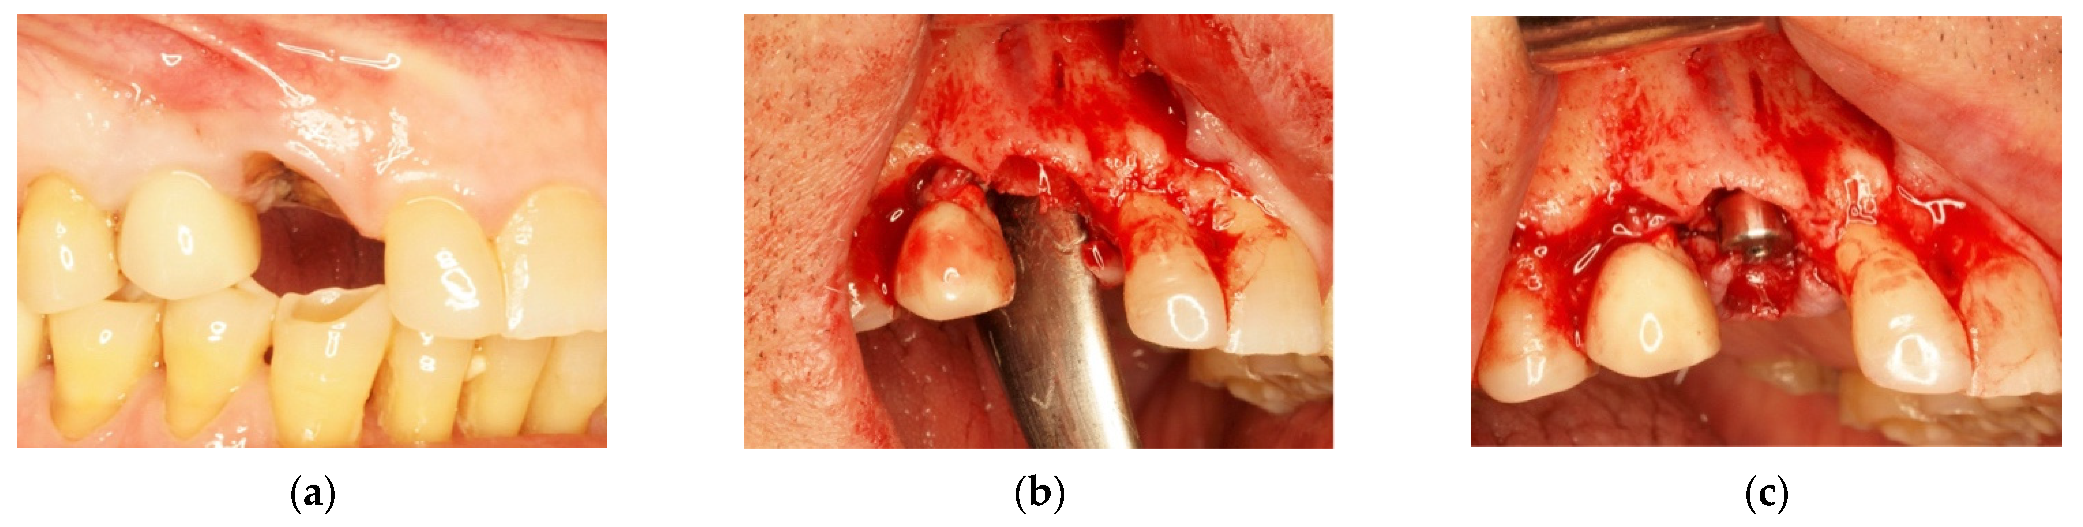

In order to rehabilitate the missing 1.3, an immediate post-extractive implant for tooth 1.3 was planned (Figure 6a–c). Blood clot was collected directly from patients (peripheral venous blood) and placed in a 5 mL vial. When the clot was thick enough due to coagulation, it was enriched with beta-tricalcium phosphate by rolling it on the surface of tricalcium granules: 1 g beta-tricalcium phosphate for every 5 mL of clot (Figure 7). Beta-tricalcium phosphate was chosen to stabilize the clot volume and for its capacity to be reabsorbed [61,62,63].

Figure 6.

(a) Edentulous tooth site 13; (b) evaluation of the alveolus; (c) implant insertion.

After the implant insertion, the enriched clot was put in the alveolar gap and protected by a shaped intra-operatory titanium foil, fixed with screws on both buccal and palatal walls. It sutured, leaving the foil exposed (Figure 8a,b).

Figure 8.

(a) Protection of the alveolus with titanium foil; (b) titanium foil; (c) follow-up at 6 months.

Six months after surgery, the high quality and stability of soft tissues was observed (Figure 8c).

The titanium barrier was removed and the growth of new bone tissue, even if not completely mature, was observed (Figure 9a). After a further 6 months, we noted how pre-existing keratinized gingiva of keratinized mucosa indicated by the arrow in Figure 9a, contributed to the formation of the adherent gingiva band as shown in Figure 9b.

Figure 9.

(a) Flap of keratinized mucosa indicated by the arrow; (b) finalization with a prosthetic crown.